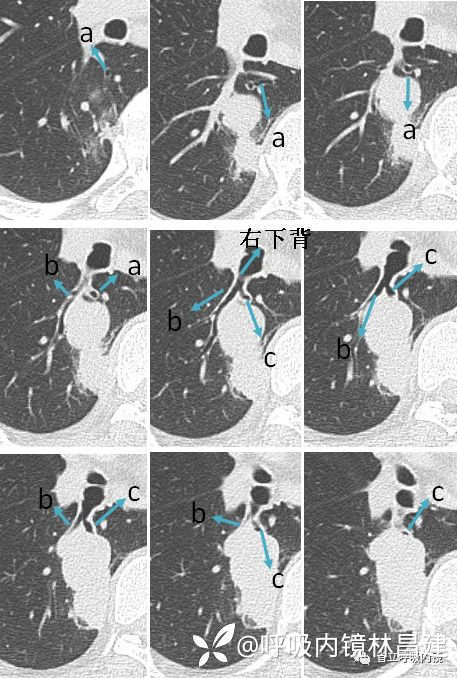

看右下叶背段支气管树可知,a、c亚段均靠近脊柱及纵隔,不同的是一个是向上走形,一个是向下走形,b亚段是远离脊柱及纵隔的向外侧发散,因此它又叫外侧支。命名顺序按照逆时针方向。

CT从上而下,依次出现a、b、c亚段。由于a亚段支气管走形是垂直于水平面的,因此CT上你可以看到一个小圆环结构,b亚段是平行于水平面的,因此CT上是呈现柱状双轨征,c亚段大多斜行于水平面,因此CT上可能呈现类似于环形跑道结构(只是打个比喻,每个人的支气管树结构变化很大,不一定都是规规整整的,有点扭曲,有个分支都是很常见的,但是先把标准的学会,再学异常的,你就能游刃有余了)。

只看这一张你是很难定位的,你需要前前后后,不断翻看,才能进行三维重建。CT从上而下,依次出现a、b、c亚段。由于a亚段支气管走形是垂直于水平面的,因此CT上你可以看到一个小圆环结构,b亚段是平行于水平面的,因此CT上是呈现柱状双轨征,c亚段大多斜行于水平面,因此CT上可能呈现类似于环形跑道结构(只是打个比喻,每个人的支气管树结构变化很大,不一定都是规规整整的,有点扭曲,有个分支都是很常见的,但是先把标准的学会,再学异常的,你就能游刃有余了)。

我们发现粗粗看上去整个背段其实一开始是分两个洞的,即两个开口,这个结构有点类似于右上叶后段的两个亚段,因为背段的a、c亚段开口靠的很近,经常合在一起靠向后方,类似于右上叶后段a亚段,背段b亚段靠前走,类似于右上叶后段b亚段。经常有人将右下叶背段b亚段当成c亚段,这是不对的,首先b亚段大都很粗,由镜头进入背段是有拐弯90度,误把b亚段看成是向下走形的c亚段,其实b亚段是跟CT层面相符的水平方向走位,c亚段是靠内后侧走的,并不是那么靠前。如果还是不能理解,有两种方法,一是用超声来明确你的推断,二是带有亚段的支气管树模型进行验证,用支气管镜伸到模型的b亚段,再从外部观察是否是在b亚段。

右中间干支气管远端三个管腔是右侧支气管的特征性结构,在CT上按照从上到下,分别是右中叶支气管、右下叶基底段、右下叶背段。如下图:

由于胸部CT跟实际解剖是左右颠倒的,即CT上左手边是右肺,右手边是左肺,于是我们需要把CT水平翻转(左右颠倒),见下图:

但是这个上中下结构还不是我们内镜下常见的结构,这是为什么呢?我们先看下内镜下这个结构是怎么样的,见下图:

在气管镜操作过程中,为了获得更大视角,往往会将气管镜顺时针旋转90度(镜头顺时针旋转,引起的图像旋转其实是逆时针,这个你可以自己动手演练一下,或者做气管镜时亲自操作一遍就懂了),因此你把CT片逆时针旋转90度,你会获得跟镜下图片表现一致的结构。所以当你再看这张示意图时,你就不会显得那么突兀了。